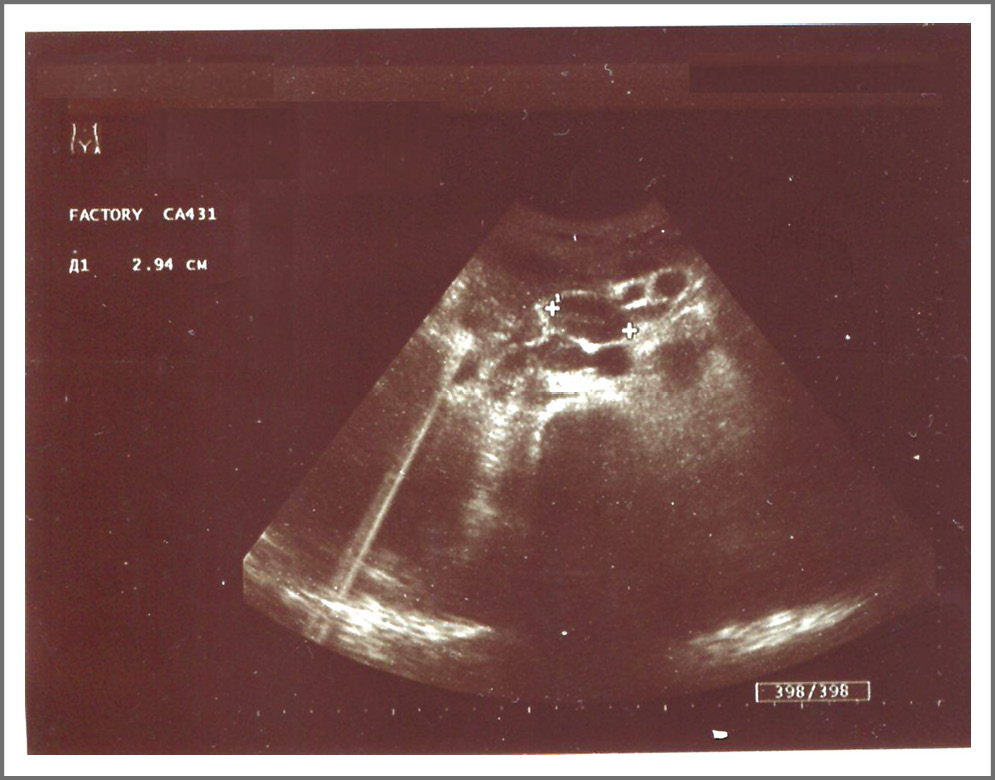

УЗИ органов брюшной полости. Печень увеличена. В правой доле (сегмент VII–VIII) изоэхогенное полиморфное образование неоднородной структуры с неровными гипоэхогенными контурами, размером 117×101×74 мм (рис. 4). Паракавально и парааортально лоцируются увеличенные лимфоузлы до 2,8 см. Компьютерная томография. Гепатоспленомегалия, признаки портальной гипертензии (диаметр v. Рorta 17 мм, v. Lienalis 15 мм). В правой доле (SVII) обнаружено образование 1,3×1,4 см с нечеткими контурами. Асцит, малый гидроторакс справа. Выраженная лимфоаденопатия чревных узлов с признаками деструкции.

Рис. 4. Образование неоднородной структуры с неровными контурами в правой доле печени. / Fig. 4. Formation of a heterogeneous structure with uneven contours in the right lobe of the liver.